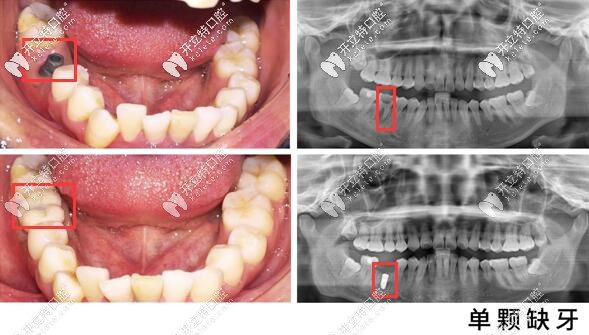

還有單顆種植牙案例可參考▼

昆明美奧口腔單顆牙種植案例